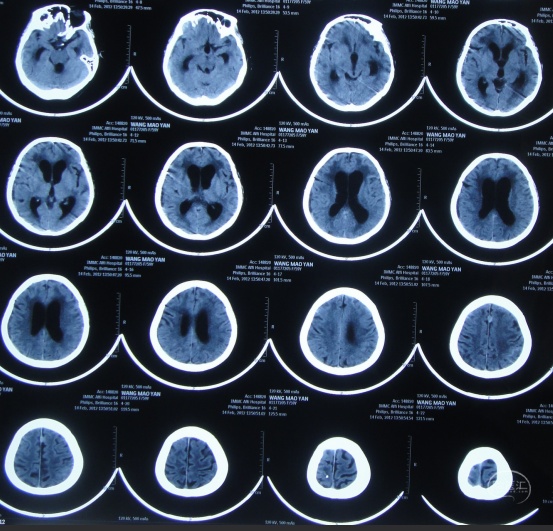

又过2月后即2011年10月14日,夜里2点起夜时突然站不稳,再次出现头昏,呕吐频繁,四肢无力,2011年10月17日第2次就诊于第2家医院:呼和浩特市某医院神经内科住院治疗,行头颅MRI(图-1)认为“末梢神经脱髓鞘病变,考虑为格林巴利综合征,轻度脑积水”。

图-1:2011年11月17日头颅核磁